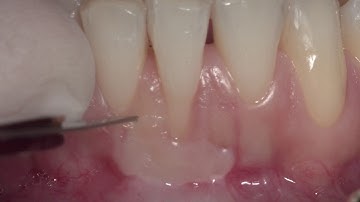

CV-78 Root Coverage - Deep Single Recession PREVIEW